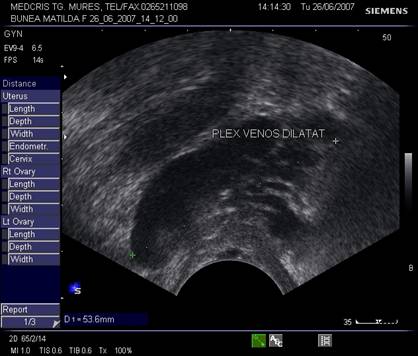

Fig. nr.395.Plex venos dilatat , parametral ( diagnostic diferential cu un chist ovarian, dificil uneori , la ecografia transvaginala )